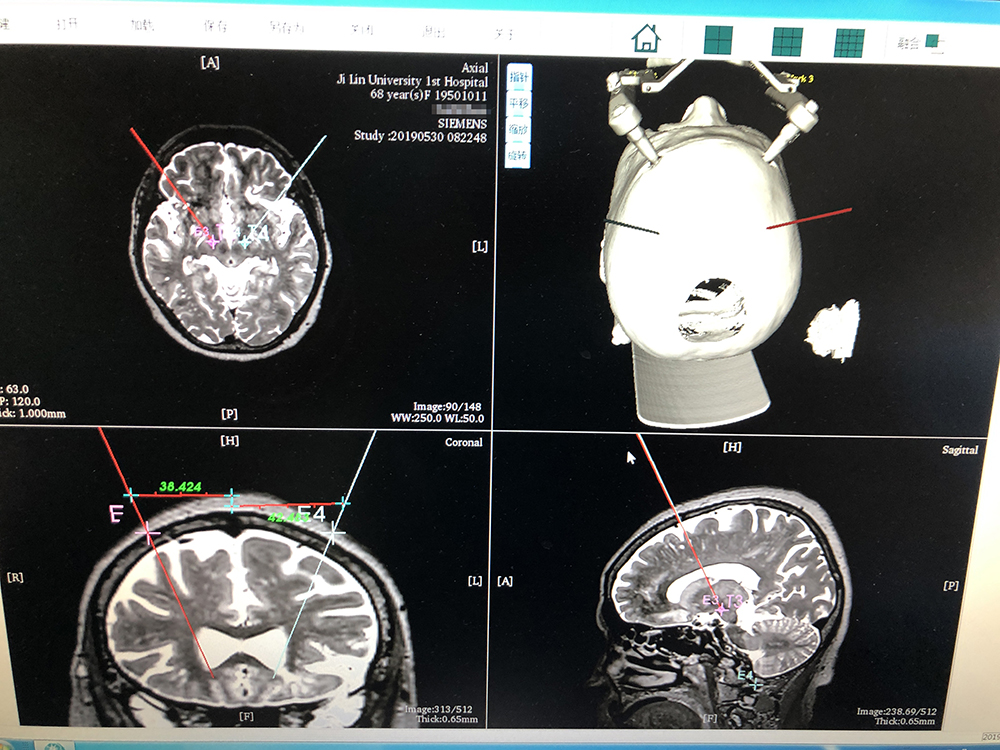

術(shù)前,邱吉慶教授借助“睿米”神經(jīng)外科手術(shù)機(jī)器人配套軟件,為患者制定雙側(cè) STN 核團(tuán)植入電極的手術(shù)路徑規(guī)劃。

借助“睿米”軟件制定手術(shù)規(guī)劃

手術(shù)規(guī)劃完成后,分別完成機(jī)械臂注冊和患者注冊,系統(tǒng)顯示注冊精度分別達(dá)到0.07和0.16,符合 DBS 手術(shù)臨床的高精度要求。為進(jìn)一步確認(rèn),利用隨機(jī)驗(yàn)證點(diǎn)進(jìn)行精度驗(yàn)證,確認(rèn)誤差在1mm以內(nèi)。